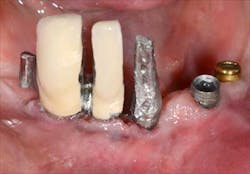

Figs. 4a, b, c: Removal of the implant prosthesis

Fig. 5: The different conical abutments ordered

Fig. 6a: Conical abutments, buccal view

Fig. 6b: Conical abutments, occlusal view

Fig. 7a: Transfer copings

Fig. 7b: The positioning of the transfer copings already shows inadequate implant positions

Fig. 7c: Transfer coping placement on site 26 is impossible: this implant will have to be removed or submerged